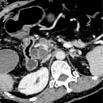

Pancreatic Axial

显示胰腺横断面影像